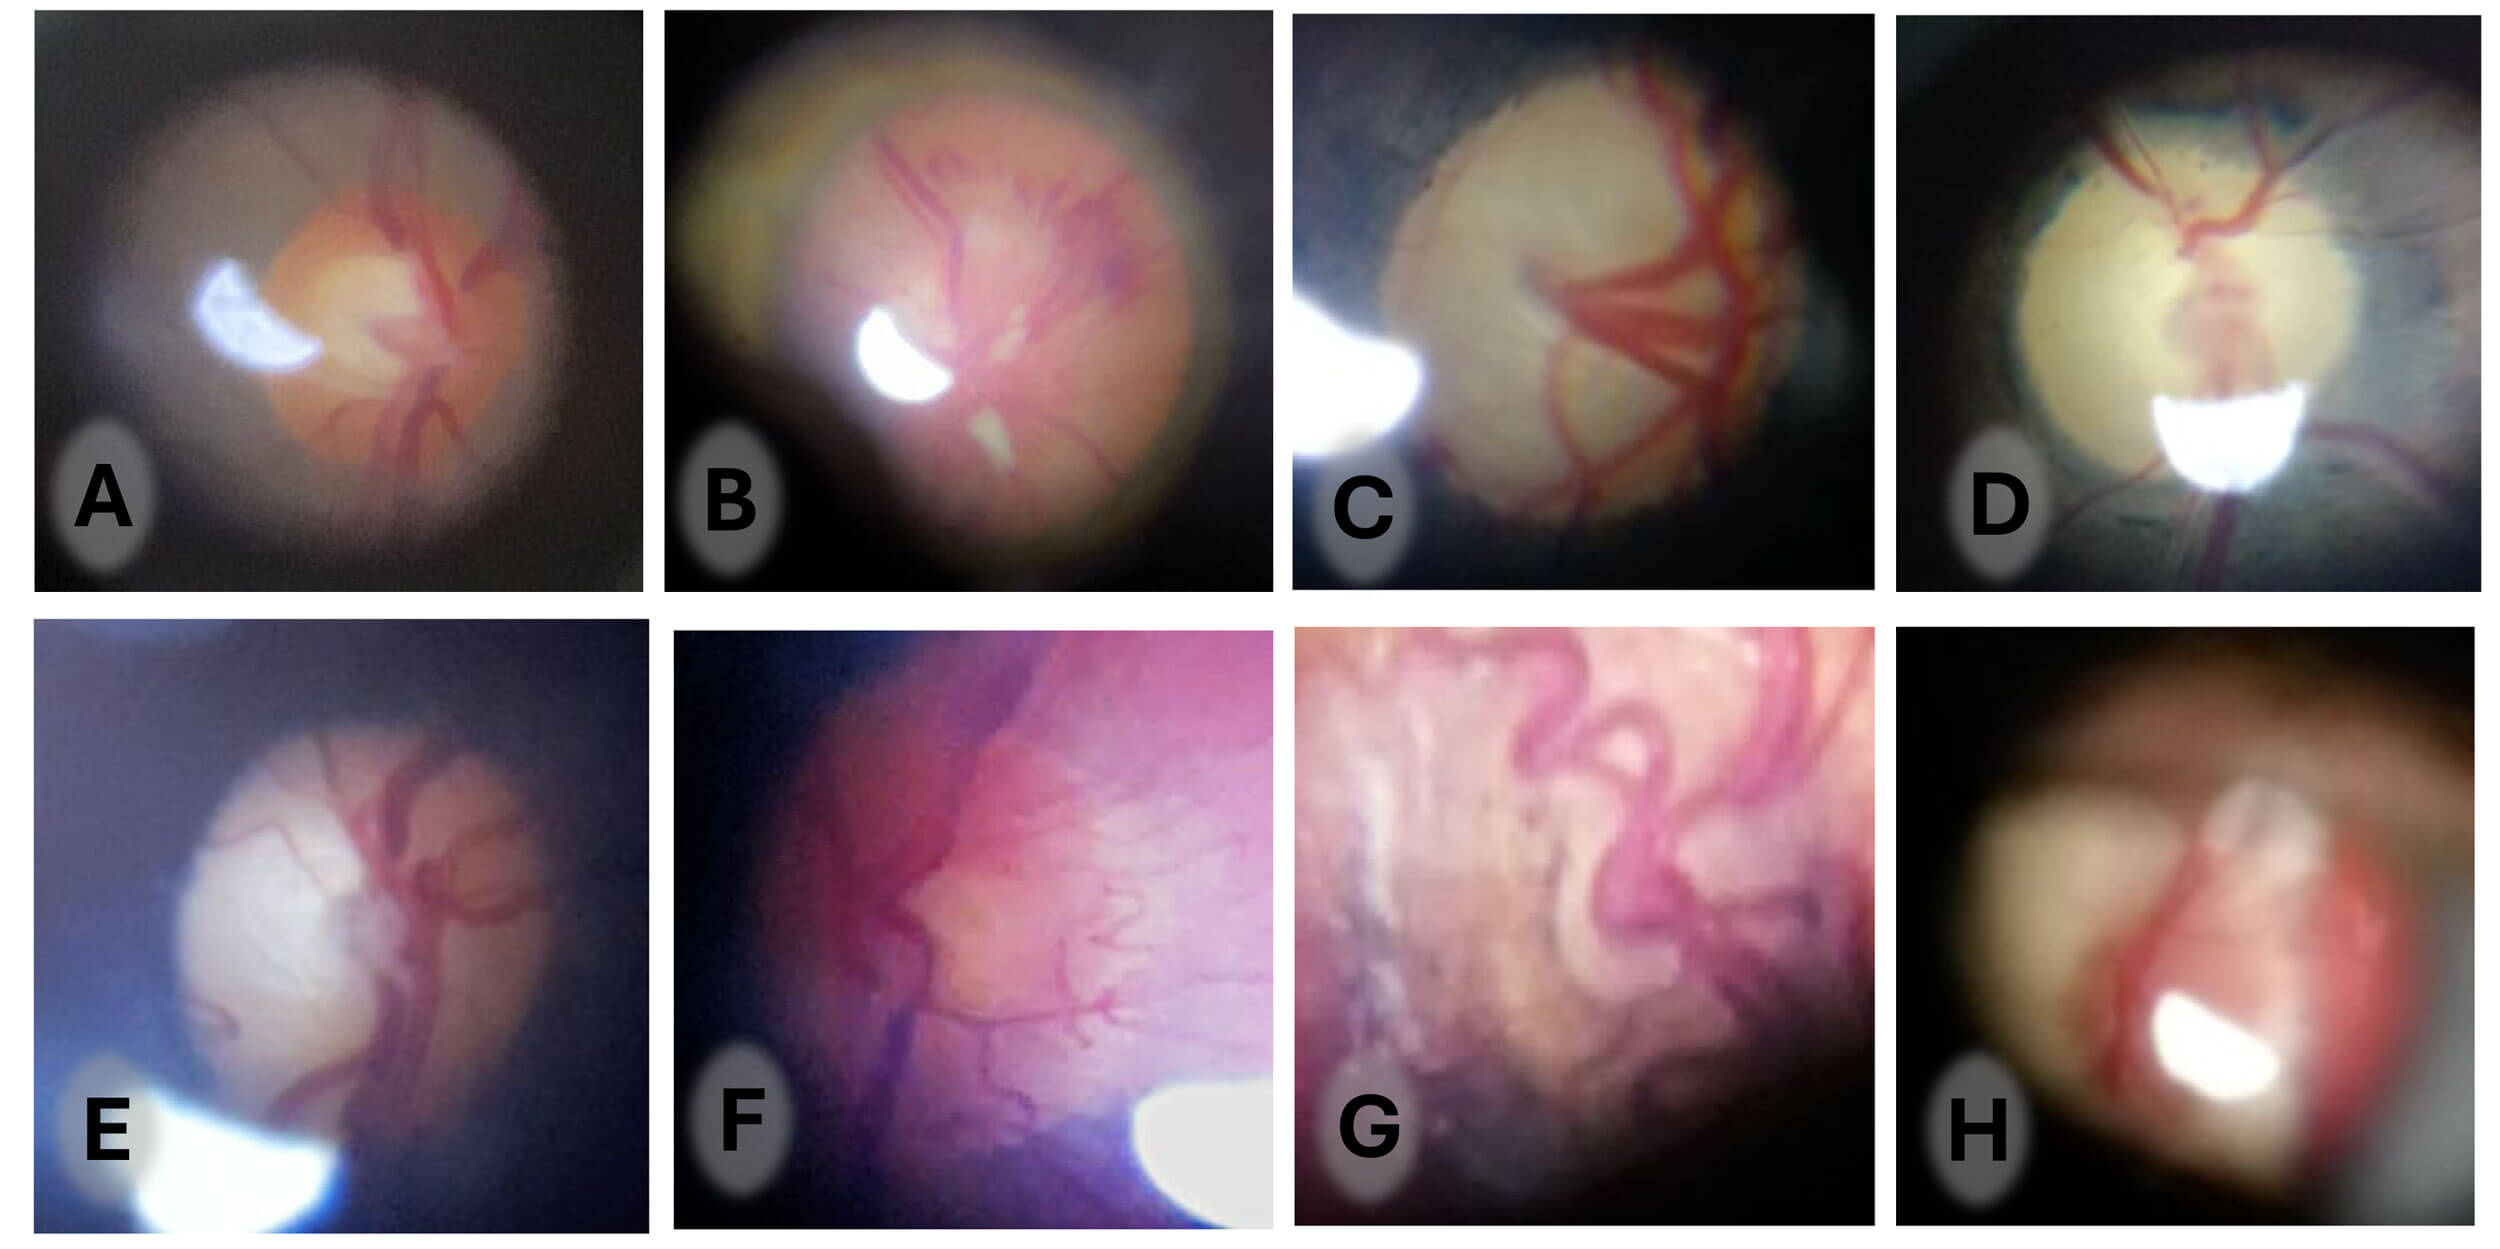

Figures 7A-H (optic nerves): (A) normal; (B) grossly swollen with haemorrhage and exudate; (C) advanced glaucomatous cupping; (D) diffuse atrophy; (E) temporal atrophy; (F) new vessels at disc; (G) gross hypoplasia; (H) myelinated nerve fibres.

When performing fundoscopy, follow the horizontal 15-degree temporal ‘flight path’ to bring the optic nerve into view. The small field but high magnification of direct ophthalmoscope allows for detailed imaging of the disc. This is essential when assessing any patient with visual disturbance or headache. The range of optic nerve signs that can be imaged is illustrated in Figure 7.